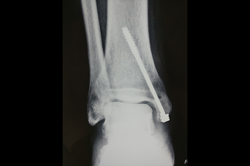

Ankle